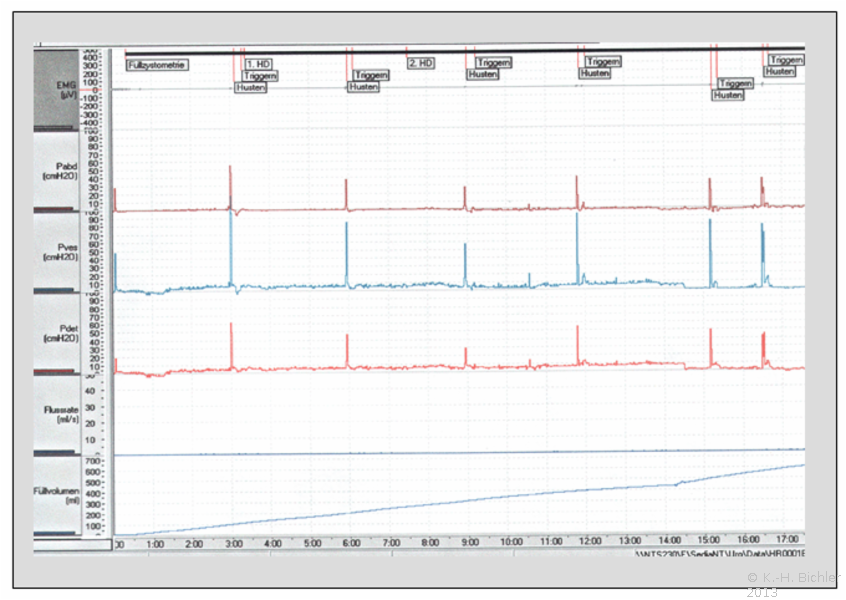

Im Rahmen der Messung werden kontinuierlich die Abdominaldrücke durch einen Druckabnehmer im Rektum und die Drücke innerhalb der Blase durch einen Druckabnehmer aufgezeichnet, es resultiert rechnerisch die Detrusorleistung als Differenzdruck. Parallel sollte das Füllvolumen der Harnblase, ein Elektromyeologramm und eine evtl. Uroflowmetrie angezeigt werden. Während der Profilometrie wird der Messkatheter unter definierten Bedingungen durch die Harnröhre zurückgezogen und zeichnet somit eine Druckkurve über den gesamten Verlauf.

Die Durchführung der Zystomanometrie unter Röntgenkontrolle erlaubt eine Aufzeichnung in den entscheidenden Phasen der Blasenfüllung und der Blasenentleerung mittels der Durchleuchtung sowie die Befundaufzeichnung auf einem Videorecorder. Während der Zystomanometrie wird über einen Katheter mit kleinem Querschnitt die Blase gefüllt und über ein 2. Lumen der Blasenbinnendruck während der Füllungs- und Miktionsphase gemessen. Ergänzend kann über ein 3. Lumen der Harnröhrendruck während der Blasenfüllung und -entleerung gemessen werden. Parallel dazu erfolgt die Registrierung des Abdominaldrucks über eine Druckaufnehmersonde im Rektum.Rechnerisch wird durch das Blasendruckmessgerät eine Differenzkurve zwischen Blasenbinnendruck und Abdominaldruck erstellt, die die reine Detrusorleistung widerspiegelt. Daneben wird über Klebe- oder Nadelelektroden ein Elektromyogramm des Beckenbodens mitgeschrieben, um die Aktivitäten des Beckenbodensmit denen der Blase zu vergleichen. Weitere vorhandene Kanäle bei der Parallelregistrierung erlauben die Aufzeichnung der miktionierten Harnmenge sowie ggf. der in die Blase instillierten Flüssigkeitsmenge. Hieraus resultieren typische Kurven, aus denen i.d.R. sehr schnell und gezielt die endgültige Diagnose hergeleitet werden kann, wie an der Beispielskurve aufgezeigt werden kann. Hier fällt sofort der zum Füllvolumen nahezu parallel verlaufende Detrusordruck auf, damit eindeutig der Nachweis einer sog. Low-compliance bladder.

Nach einem kompletten Füllungs- und Entleerungszyklus kann der Messkatheter unter definierten Bedingungen aus der Blase über die Harnröhre langsam zurückgezogen werden. Damit wird ein sog. Urethradruckprofil aufgezeichnet, welches die in Ruhe gemessenen Drücke in der Harnröhre mit den Drücken in der Blase vergleicht. Erfolgt diese Urethraprofilometrie unter gleichzeitiger abdomineller Druckbelastung (Husten, Pressen) spricht man von einer Urethrastressprofilmessung. Die parallel geführte Viedeoaufzeichnung der Durchleuchtung zeigt, da die Blase mit verdünntem Kontrastmittel gefüllt wird, einen evtl. auftretenden vesikoureteralen Reflux während der Füllungsphase und die Konfiguration des Blasenhalses und der Harnröhre während der Miktionsphase. Mit den modernen Blasendruckmessgeräten sind eine Nachbearbeitung der Befunde sowie ihre EDV-gerechte Speicherung möglich. Die Standardbedingungen für eine Zystomanometrie sind international vereinheitlicht. Die Zystomanometrie wird vorwiegend in sitzender Patientenposition durchgeführt, kann aber auch liegend, besonders bei tetraplegischen Patienten, durchgeführt werden.

Urodynamisch ergeben sich bei den verschiedenen Störungen entsprechende Kurven (Abbbildung HG3).

Ein nahezu starrer Detrusormuskel verhindert die Dehnung bei Füllung mit der Folge eines füllungsproportionalen Druckanstieges [proportionaler Verlauf von p ves (Druck innerhalb der Harnblase) und Füllungsvolumen].